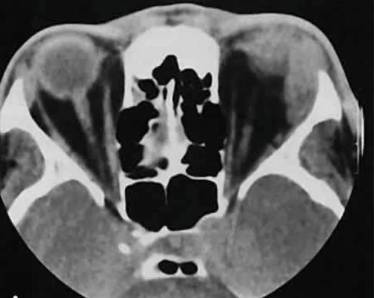

Диагностика

При пальпации шеи отмечается острая боль, мышцы уплотнены, может присоединяться покраснение и гиперемия. Для уточнения характера воспалительного процесса и его возбудителя производят анализ крови из пальца на стерильность и химический состав. Дополнительные методы исследования:

- Электромиография – показывает степень поражения нервных волокон, проводимость которых регулирует способность мышцы сокращаться.

- УЗИ мышц – помогает определить степень выраженности воспалительного процесса в шее.

- Рентгенография – помогает исключить вероятность развития патологий костной ткани.